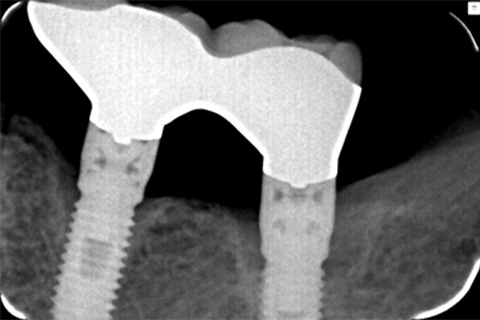

| 患者さま情報 | 74歳 男性 |

|---|---|

| 治療期間 | 2018年11月~441日間 |

| 治療費 | インプラント一本 15,000円(税抜) |

| 治療詳細 | 10年前に他医院にてインプラント治療を完了。 当医院にて2018年11月9日にインプラント周囲炎の治療を行う。 ペリソルブとSRP、Er-Yagレーザー照射をフラップ形成下で行った。グラフトレス症例。 |

| 治療におけるリスク・副作用 | ・術後のプラークコントロールが不良の場合、術後感染を起こす可能性があります。 ・ペリソルブの生体に対する安全性は、厚生労働省に認可されています。 |